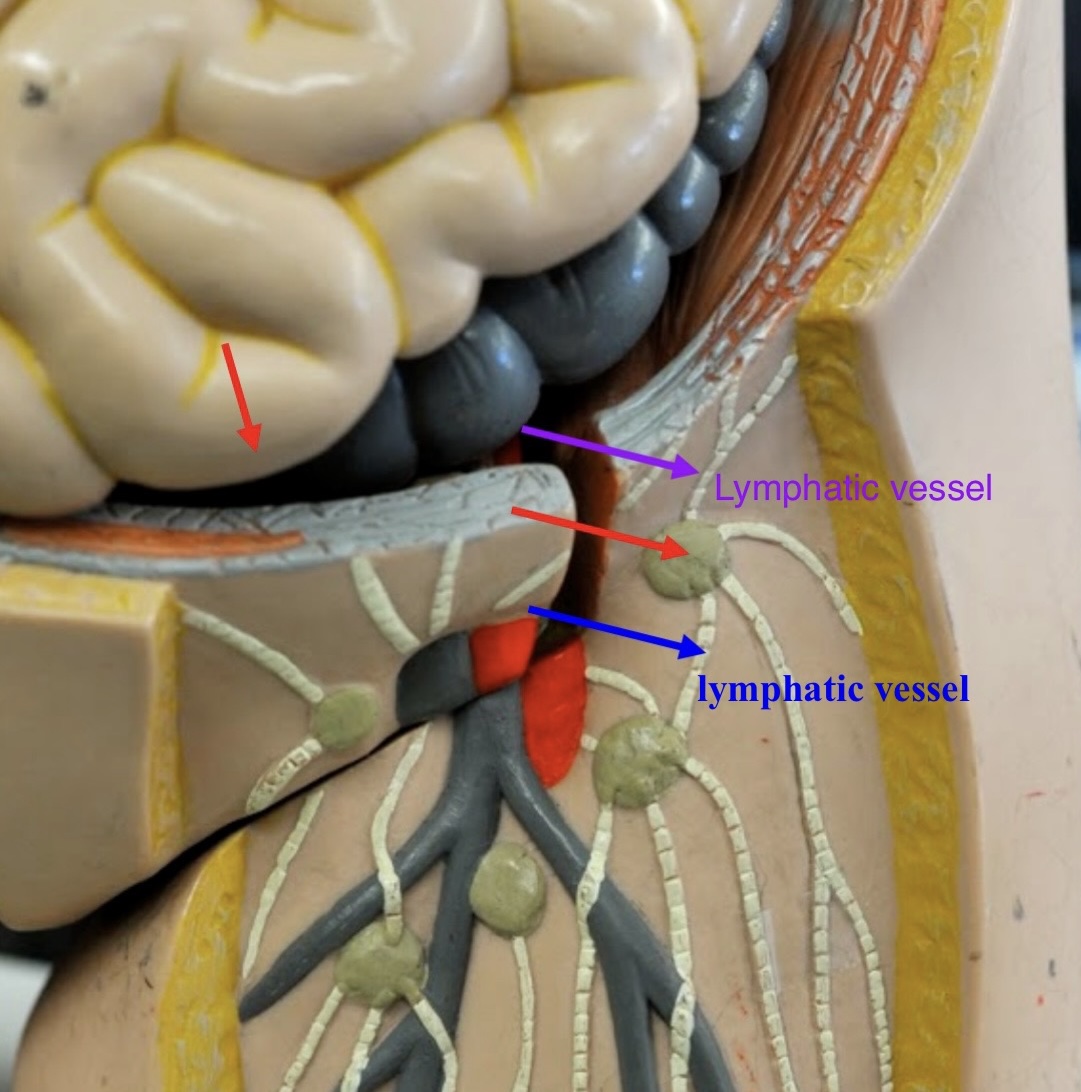

lymphatic vessels

large vessels with valves, which collect and carry lymph to lymph nodes

lymph

fluid that circulates through the lymphatic system, containing white blood cells (mainly lymphocytes), proteins, and other substances

afferent lymphatic vessels (lymph node)

Entrance on the lymph node for lymphatic vessels to bring lymph fluid

hilum (lymph node)

An indentation where blood vessels and nerves reach the lymph node.

efferent lymphatic vessels (lymph node)

the vessels leaving the concave hilum of the lymph node carry lymph away and onward to the venous system.

Are there more afferent or efferent lymphatic vessels?

Afferent lymphatic vessels generally outnumber efferent lymphatic vessels.

lymphatic capsule (lymph node)

The connective tissue that surrounds and protects the lymph node.

trabeculae (lymph node)

the extends inward and partition the interior of the node.

What is the advantage of the fact that afferent lymphatic vessels outnumber efferent lymphatic vessels?

This creates a bottleneck effect that slows down the flow of lymph within the node. This creates more time for examination of the lymph.